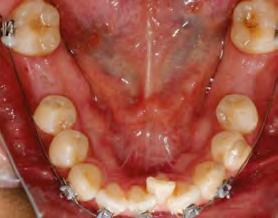

52 | SONRIENDO AL FUTURO

Tratamiento ortodóncico en paciente adulto tratado con extracciones de primeros molares permanentes. Reporte de caso

Tratamiento ortodóncico

en paciente adulto tratado con extracciones de primeros molares permanentes. Reporte de caso